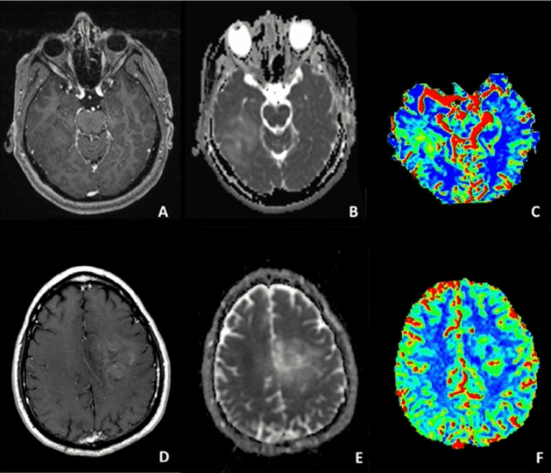

SWI Conceitos Básicos

Continue a ler este conteúdo – e todos os outros que a Neurosky oferece para assinantes. Tópicos e assuntos para você aprofundar o seu conhecimentoAcesso…